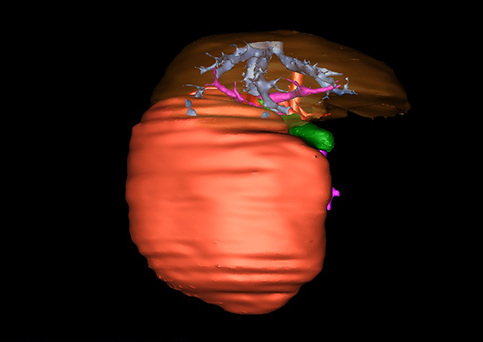

目前常用的检查方法有B超检查、CT、MRI、血管造影等。与其它的腹部肿块的诊断不同,对于小儿肝母细胞瘤血管造影具有重要的意义,可以作为手术前介入治疗的手段,也可为手术提供非常有效的影像学指导,但技术要求高,操作较复杂,且给患儿带来一定的痛苦。近年借助计算机辅助手术系统进行CT原始影像三维重建、手术规划和计算机虚拟手术技术,为精准肝脏手术提供了极为有效的技术支持。

近年来由于数字医学的发展,基于可视化三维重建技术的计算机辅助手术系统极大推进了小儿肝脏肿瘤的精准手术的进步。可以立体透视肝脏解剖、精确掌握肝段的边界、精确测算肝段乃至任意血管所支配的功能体积、准确定位病灶及其与邻近血管的解剖关系,最终对不同手术方案进行比较、筛选和优化。因此,计算机辅助手术规划系统是实现精准肝切除的有力辅助工具,是未来数字外科、精准外科等21世纪外科新理念的重要技术支撑。

计算机辅助手术规划系统具有良好的操作可行性、计算准确性和三维显示效果,可半透明、交互式显示真实的肝内立体解剖关系和空间管道变异,准确计算肝内管道的直径、走行角度,两点间的垂直距离,和任意血管的支配或引流范围等传统二维影像无法获取的信息,有助于实施个体化手术,提高了手术的确定性、预见性和可控性。计算机辅助手术规划系统可直观显示预留肝脏的结构和功能,并可通过虚拟切割功能辅助术者对手术方案进行蹄选和优化,系统评估手术风险和制定对策,改变了部分二维规划的术式和切除范围,使部分二维规划认为不能切除的患者成功手术,提高了手术的根治性、安全性和病变的可切除性,更加符合精准肝脏外科的术前规划要求。详见第11章。

随着计算机技术及影像检查技术的不断发展,以精确的术前影像学和功能评估、精细的手术操作为核心的精准肝切除技术日益受到重视。基于数字医学的计算机辅助手术技术(computer-assisted surgery,CAS)则是实现肝脏精准手术操作的基础。计算机辅助手术系统(CAS)可将术前二维(two dimensional,2D)的CT/MRI影像数据进行三维(three dimensional,3D)重建,建立个体化的肝脏三维解剖模型,清晰显示肝脏内脉管系统的走行及解剖关系,还原病灶与其周围脉管结构的立体解剖构象,准确地对病变进行定位、定性和评估,制定合理、定量的手术方案,实施个体化的肝脏血管取舍分配方案及实施精准肝脏手术。一般认为CAS包括:创建虚拟的患者的图像;患者图像的分析与深度处理;诊断、手术前规划、手术步骤的模拟;术中实时导航。应用本技术后,由于可以更清晰地看出肿瘤的界限,特别是根据肝血管的显影,判断出肿瘤与门静脉及肝静脉的关系以在手术前较准确地估计出手术成功切除的可行性。以往部分根据普通强化CT判断无法手术的病例而被评估为可以成功切除并手术成功。